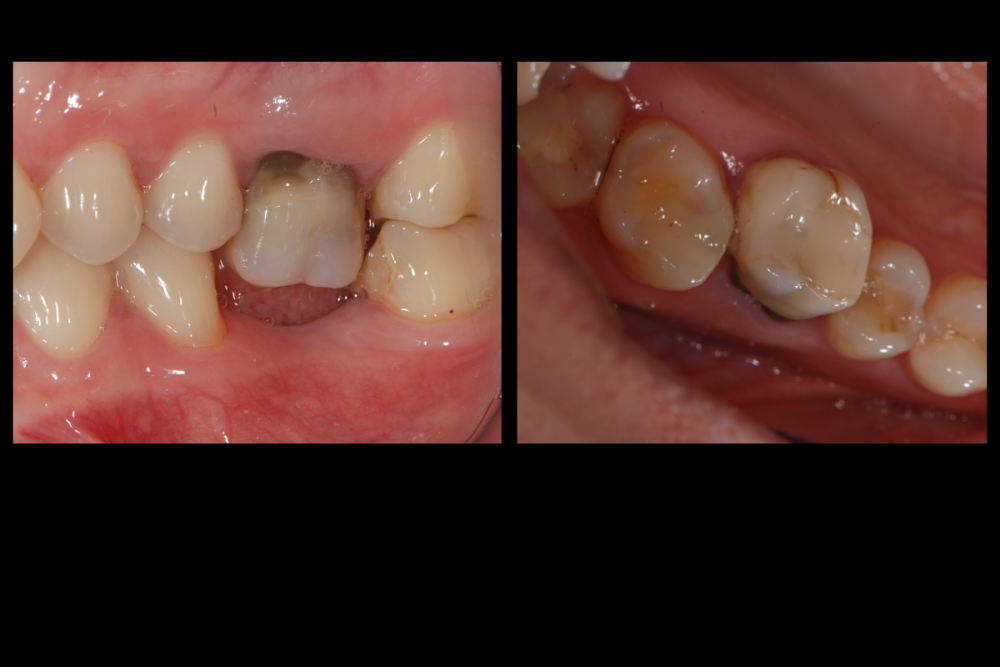

Карен Аванесов Опубликовано 10 ноября, 2021 Автор Поделиться Опубликовано 10 ноября, 2021 Придерживаясь правил форума, второе сообщение содержащее фотоматериал выдержанно в лучших традициях русской словестности, без сквернословия и непонятных иностранных слов, без применения шовного материала, широких формирователей десневой манжеты, без мягкотканной и прочей аугментации (наращивание костей что то все же не звучит прилично)), а самое главное, время затраченное на всю операцию 60 минут (имплантаты на нижней челюсти установил по лазерной технологии, без разрезов, Лазер - сила!). Время ожидания до ортопедического этапа 3 месяца. 6 1 Ссылка на комментарий